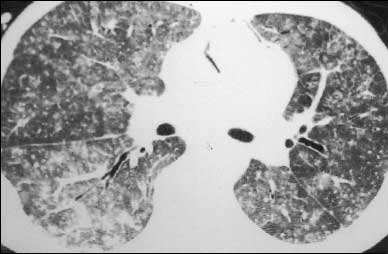

历次大规模传染病在人类历史上 , 有多次导致大流行的传染病 。 在人类对病毒和细菌了解还不充分的年代 , 肺结核病就已经开始在人与人之间传播了 。 肺结核是由结核分枝杆菌所引起的疾病 , 在中国也称为“肺痨” 。 可以说 , 这种疾病伴随着整个人类文明的发展 , 这种疾病的历史可以追溯到数千年前 , 并且一直持续到今天 。